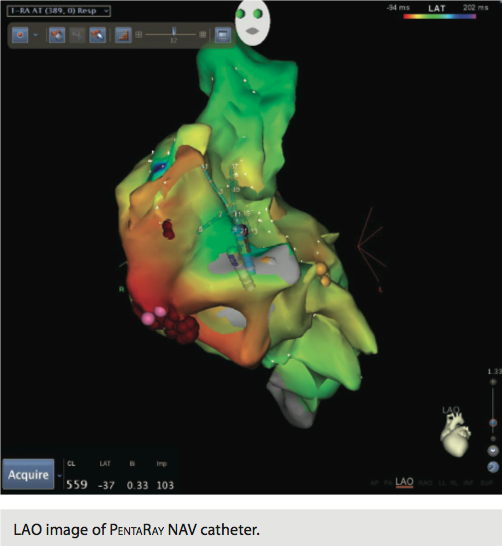

Using the Carto 3 three-dimensional electroanatomical mapping system and the Biosense Webster MEM, we performed fast activation mapping of the entire right atrium. We took approximately 400 points with the PentaRay NAV catheter in less than 10 minutes. Review of these points demonstrated that the earliest atrial electrogram (when compared to CS poles 8-7) was seen at the lateral tricuspid annulus.

Next, with pacing in the high right atrium, we were able to induce a different atrial tachycardia, which appeared to be emanating from the posterolateral tricuspid annulus, approximately 4 cm away from the site of the original tachycardia. Again, using the PentaRay NAV catheter, we remapped this tachycardia in the right atrium. The area of earliest atrial activation on this occasion was at the posterolateral tricuspid annulus, and atrial electrograms achieved at this site preceded the coronary sinus reference electrode by 87 msec. They also preceded the onset of the P-wave by 40 msec.

Final impressions were focal atrial tachycardias emanating from the lateral tricuspid annulus and the inferolateral tricuspid annulus. A total of 19 applications of radiofrequency energy were delivered, all guided by three-dimensional electroanatomical mapping. Total fluoroscopy time utilized was 22 minutes and 16 seconds with 280 mGy — far below the reportable 2500 mGy. The reduced fluoroscopy time was attributed to the rapid mapping achieved with the PentaRay NAV catheter. Total procedure time (from stick to stop) was three hours and 38 minutes.

Our initial impression of this new technology was very favorable. The PentaRay NAV catheter facilitated an accurate and fast construction of the right atrial map. The initial map guided us to the tricuspid annulus and quickly identified it as the source of the arrhythmia. During this case, an additional atrial tachycardia was noted and two separate maps were needed. Previously, mapping of multiple atrial tachycardias was extremely time-consuming because of the need for multiple maps. The PentaRay NAV catheter allowed us to take 400 points in less than 10 minutes and formulate a single map, when other technology would have taken 45 to 60 minutes to achieve the same result. In summation, two atrial tachycardia maps of at least 400 points each were constructed in less than 20 minutes during this case.